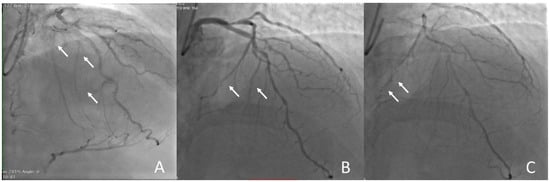

5.2. Coronary Perforation

5.3. Donor Vessel Injury